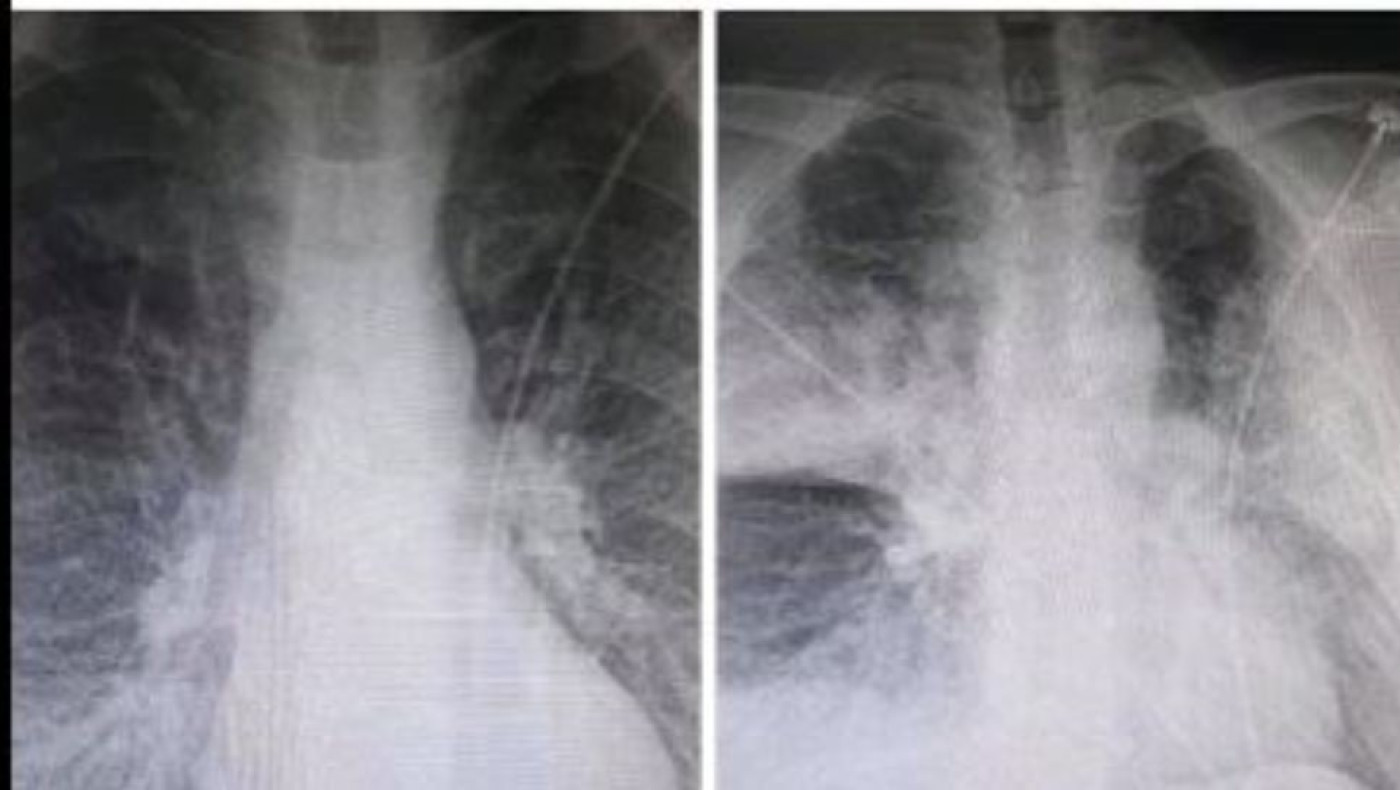

Σχολιάζοντας την ανησυχητική ανάρτηση του ακτινολόγου από το ΚΑΤ, που ανέβασε δύο ακτινογραφίες στο Facebook μέσα από τις οποίες αποτυπώνεται η ραγδαία επιδείνωση που προκαλεί ο κορωνοϊός στους ασθενείς, ο καθηγητής Πνευμονολογίας - Εντατικής Θεραπείας της Ιατρικής Σχολής του Πανεπιστημίου Αθηνών, Θεόδωρος Βασιλακόπουλος, δήλωσε ότι υπάρχουν περιπτώσεις ασθενών των οποίων η καλή εικόνα του αναπνευστικού συστήματος διαρκεί αρκετές ημέρες, αλλά αίφνης την 8η, 9η, 10η ημέρα εκδηλώνουν την επιπλοκή.

«Η ανάρτηση δείχνει μια λοίμωξη του αναπνευστικού, μία πνευμονία, που σε λίγες ώρες μετεξελίσσεται σε μια επιπλοκή της πνευμονίας που ονομάζεται οξεία πνευμονική βλάβη και στη σοβαρότερη μορφή της (ονομάζεται) Σύνδρομο Αναπνευστικής Δυσχέρειας του ενήλικα. Δεν πρόκειται για κάτι σπάνιο στις λοιμώξεις του αναπνευστικού ούτε και στη λοίμωξη που προκαλεί εν προκειμένω ο κορωνοϊός. Εκδηλώνεται και στην εποχική γρίπη και σε άλλες λοιμώξεις. Το Σύνδρομο Αναπνευστικής Δυσχέρειας είναι μία από τις βασικές, σοβαρές αιτίες που θα οδηγήσει κάποιον ασθενή με λοίμωξη σε Μονάδα Εντατικής Θεραπείας (ΜΕΘ). Αλλά και μια από τις αιτίες που ασθενής νοσηλευόμενος σε ΜΕΘ μπορεί να πεθάνει» επεσήμανε ο κ. Βασιλακόπουλος.

Όσον αφορά στη διάρκεια που χρειάζεται για την εμφάνιση της υποξαιμίας, ξεκαθάρισε ότι δεν υπάρχει συγκεκριμένη. «Υπάρχουν ασθενείς που έχουν εμφανίσει την οξεία εικόνα, ακόμη και σε λίγη ώρα, από την στιγμή που εμφανίστηκαν στο νοσοκομείο και υποβλήθηκαν σε ακτινογραφία. Υπάρχουν άλλες περιπτώσεις ασθενών που η καλή εικόνα του αναπνευστικού συστήματος διαρκεί αρκετές ημέρες, αλλά αίφνης την 8η, 9η, 10η ημέρα εκδηλώνουν την επιπλοκή».